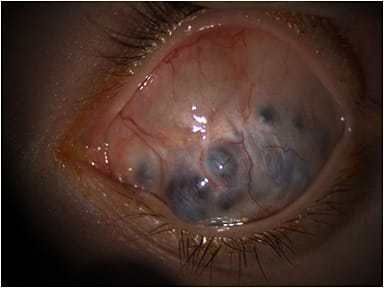

All testing for OD revealed normal findings with 20/20 uncorrected visual acuity. OS had no light perception with 4+ afferent pupillary defect (APD). Severe vascularized opacification was found on the OS cornea with multiple areas of elevation and uveal show. A tube shunt was observed superior nasally, but unable to assess patency. The intraocular pressure was 13 mmHg and 20 mmHg for OD and OS, respectively. Dilated fundus examination for OS was not able to be viewed. B-scan ultrasonography was performed and found vitreous degeneration with a grossly flat retina.

Figures 1 and 2 show the patient in primary and downgaze, respectively. Figures 3 and 4 demonstrate the corneal staphyloma using anterior segment optical coherence tomography. This patient was diagnosed with corneal staphyloma and minor scleromalacia secondary to surgical complications from fetal alcohol syndrome. She deferred enucleation and/or ocular prosthetic consult.